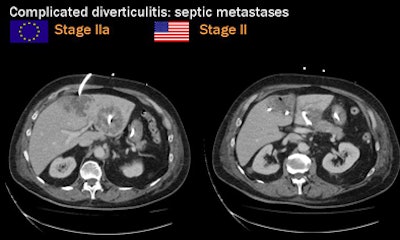

![]() |

| Locally complicated cases with hemorrhage and perforation often reveal a "lucky hat" sign, indicating active migration of omental fat that drives local inflammation. Extracolonic abscess formation indicates stage IIB disease by the Hanson/Stock staging method and stage II by the modified Hinchey system. |

"Once we have distant metastatic [infection] sites, it will be stage II according to the Hinchey classification, although the local findings are minimal," Rogalla said. "When we see abscess formation, sometimes the sigmoid colon looks almost normal, but in almost all cases that's the source of the infection." Once again the abscesses can be drained at CT-guided fluoroscopy, he said.